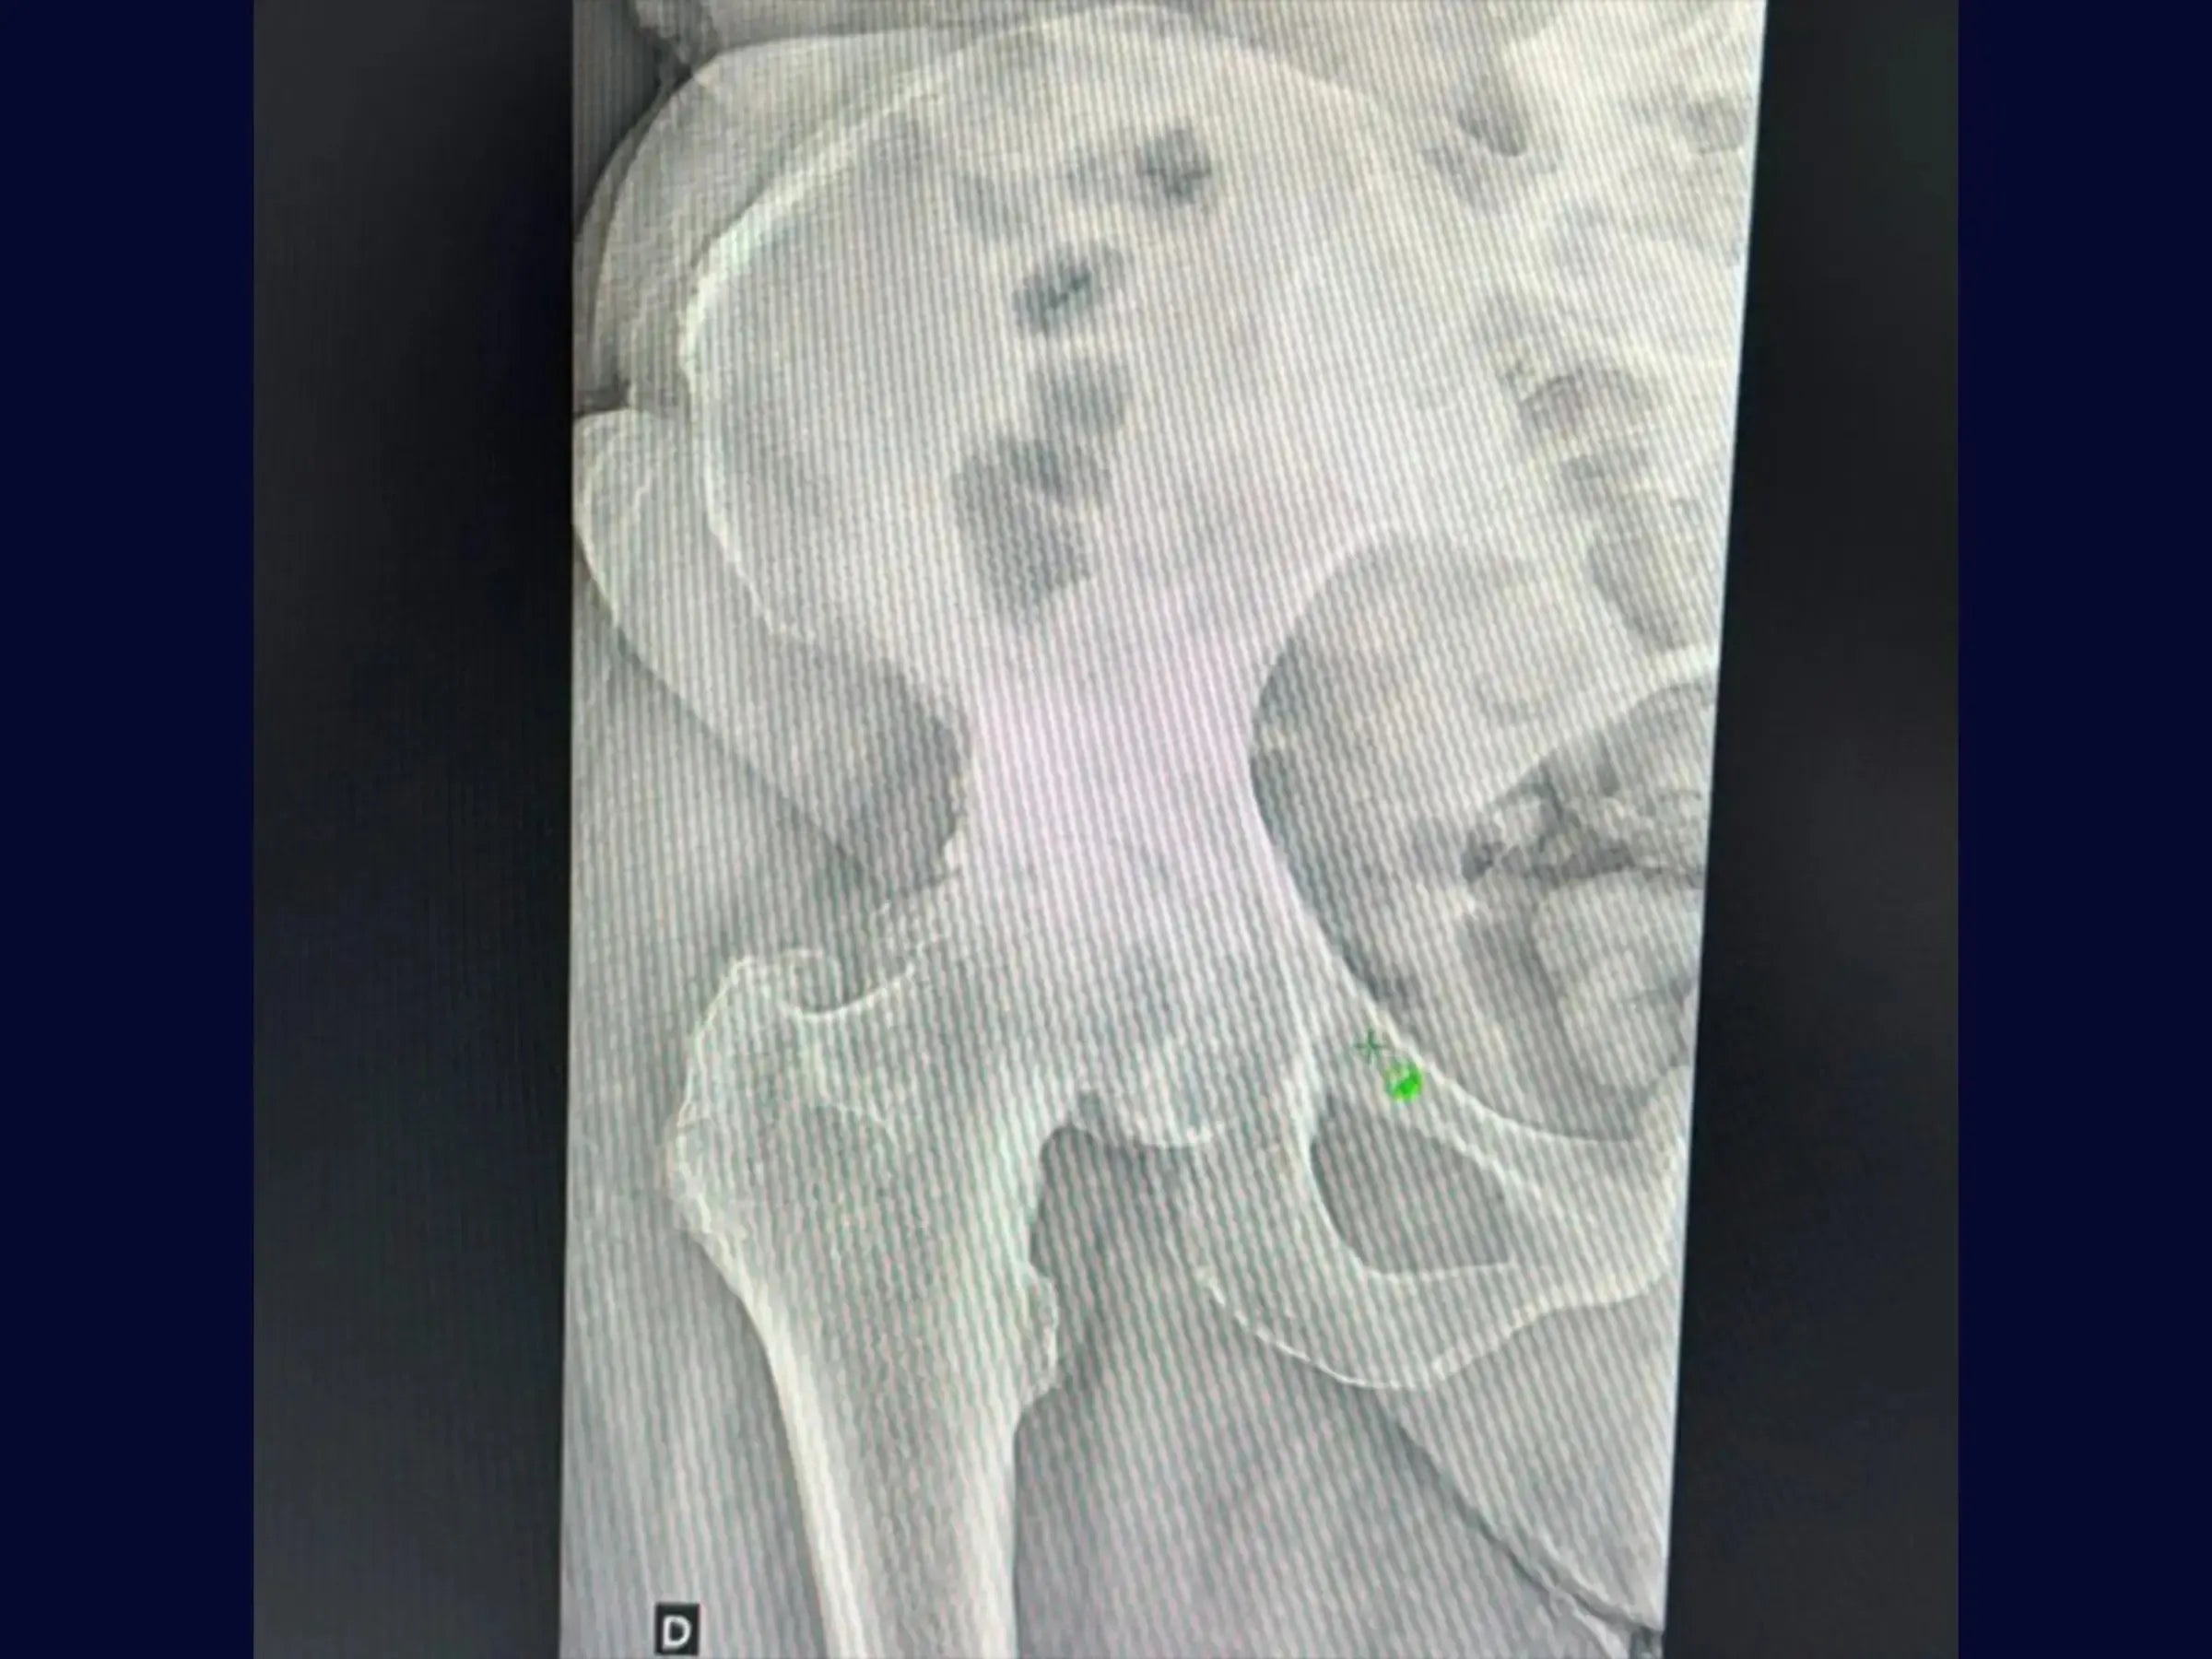

- Posicionamiento Estratégico del Paciente y Demarcación de la Piel: Metodología para el posicionamiento en decúbito lateral con flexión de cadera a 45 grados e identificación precisa de puntos de referencia anatómicos (espina ilíaca posterosuperior, diáfisis femoral, vértice del trocánter) para optimizar el campo quirúrgico.

- Exposición controlada y preservación anatómica: técnicas para abordar los rotadores externos y la capsulotomía, incluido el manejo del piriforme acortado en casos de osteoartritis y el uso del retractor Hohmann de 45 grados para levantar el glúteo medio y mínimo.

- Luxación segura y osteotomía precisa: abordaje sistemático de la luxación de cadera con retractor posicionado en el trocánter menor y demarcación de la osteotomía.